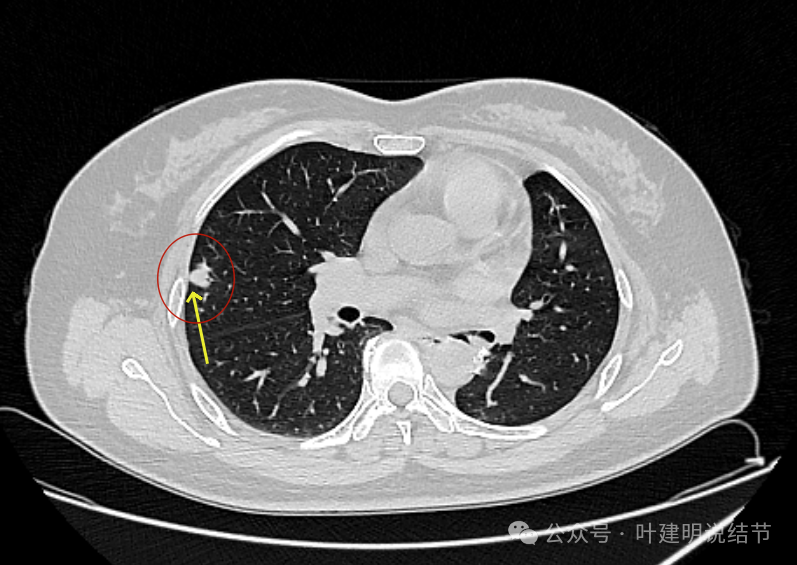

先看2024年5月时的片子:

病灶出现 ,边缘略显毛糙,有小血管进入,也见毛刺或小棘突征。

边缘不平,实性密度,贴着胸壁,胸壁处无明显增厚或胸膜反应。